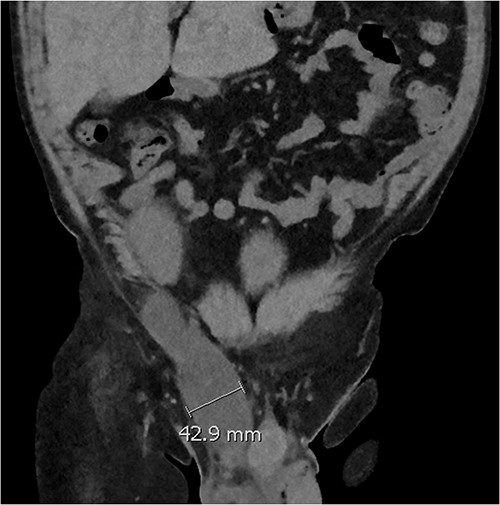

Three weeks postoperatively, the patient noticed a progressively enlarging right groin mass and associated discomfort. His examination was notable for a firm non-pulsatile non-reducible inguinal mass with no bowel sounds. He proceeded to have a CT Kidney, Ureter, Bladder (KUB), which revealed a small amount of perinephric collection (20 Hounsfield unit) marginating the posteromedial aspect of the transplant lower pole with a further fluid collection distending the right inguinal canal (10 Hounsfield unit) (see Fig. 1). The inguinal fluid pocket was localized with bedside ultrasound and 30 ml of clear fluid was aspirated with immediate symptom relief. The patient noticed reaccumulation of the fluid after a week and became symptomatic of pain again by the end of the third week.

Coronal CT image showing a dominant fluid collection extending off the lower pole of the transplant kidney into the right inguinal canal.